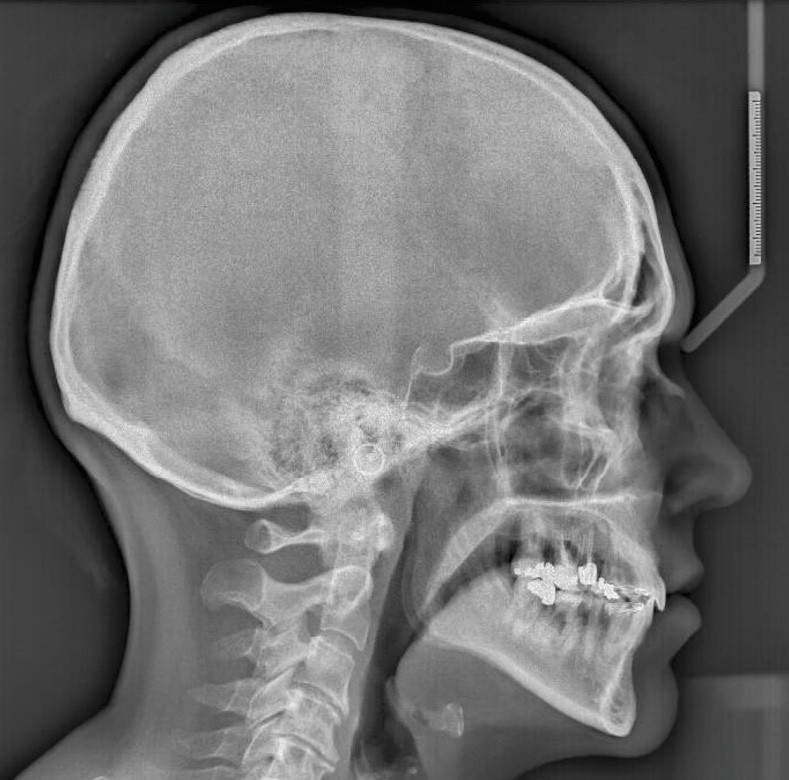

L’examen radiographique (fig. 3-5) nous indique une Classe I squelettique de Ballard (ANB 0°) sur un schéma facial à tendance hyperdivergent (FMA 28°). L’analyse céphalométrique confirme la vestibulo-version incisive (I/SN 111° ; IMPA 94°). La lyse osseuse est généralisée.